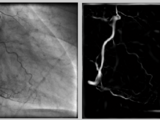

Hessian based Frangi Vesselness filter

This function uses the eigenvectors of the Hessian to compute the likeliness of an image region to contain vessels or other image ridges , according to the method described by Frangi (2001)

- The 2D example detects vessels in an x-ray image